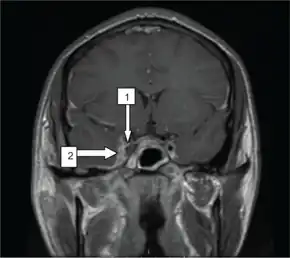

| Oblique section through the cavernous sinus. | |